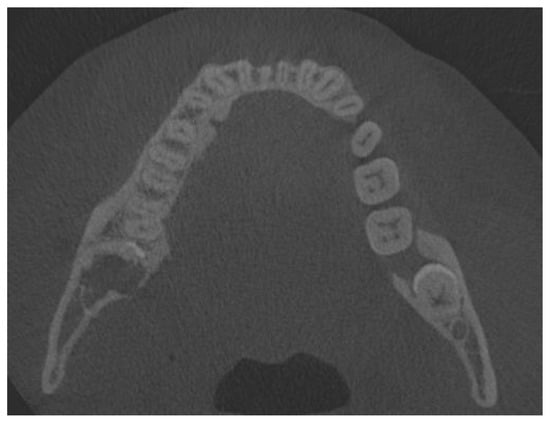

The patient was a generally healthy male without any history of surgery, illness, or surgery in the oral cavity region. The occurrence time of this lesion and its growth duration were not established. All of the surrounding anatomical areas and spaces were free of any diseases. Routine panoramic radiography (panx) and cone-beam computed tomography (CBCT) excluded any major changes in the bone near the tumour and excluded any potential odontogenic cause of the MRT swelling. The cortical parts of the bone in the CBCT study were also normal. No bone erosions, infiltrations, tooth resorptions, or bone swelling were detected (Figure 3). Because of the lack of substantial bone involvement, except for the impacted right mandibular wisdom molar with visible signs of bone ankylosis, suspicion of a nonodontogenic tumour was established.

Because of the lack of clear margins after the excisional biopsy and the presence of some of the retained wisdom teeth, a decision was made to radicalise the first procedure. The main focus was to maintain good soft tissue margins, and the remaining wisdom teeth were removed, followed by the use of an osteoalveoplasty procedure. Control CBCT and panx evaluation revealed that the bone and tooth status after the first procedure was good and that the patient had healed properly (Figure 4, Figure 5 and Figure 6).

Figure 4. Cone-beam computed tomography one month after biopsy. Half of the fully retained third molar is visible.